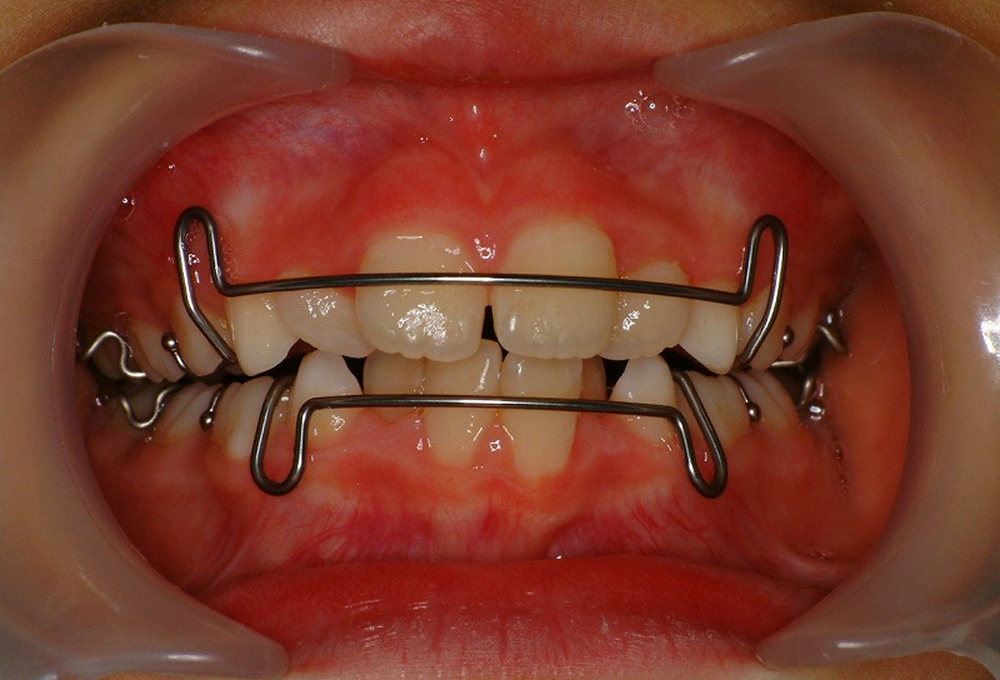

③正面観

②拡大床装着